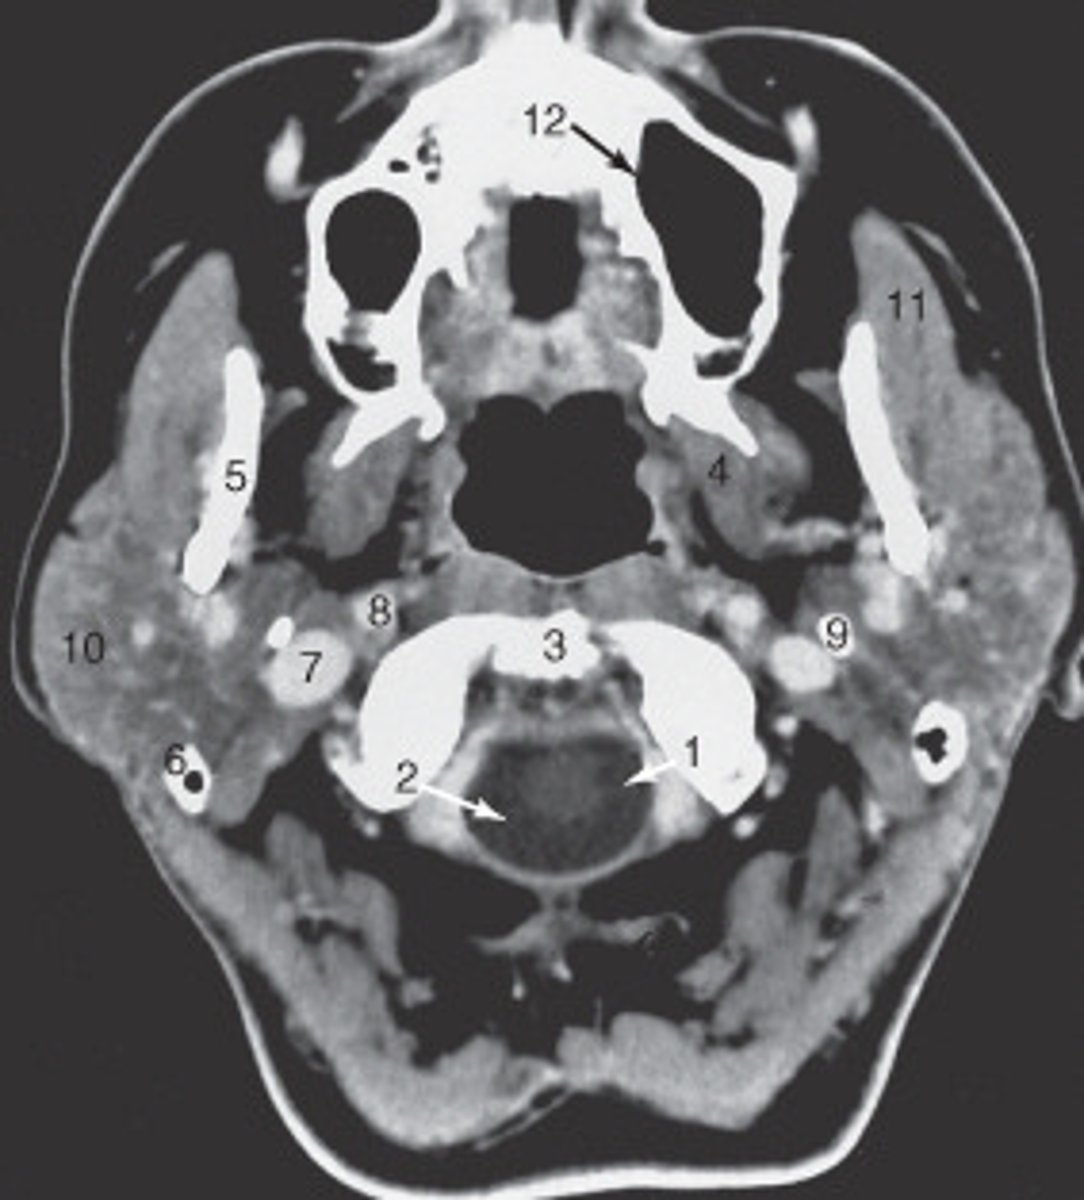

the nasal septum is labeled:

<p>the nasal septum is labeled:</p>

the mastoid air cells are labeled:

<p>the mastoid air cells are labeled:</p>

the structure labeled 6 is the:

<p>the structure labeled 6 is the:</p>

the structure labeled 5 is the:

<p>the structure labeled 5 is the:</p>

the zygoma is labeled:

<p>the zygoma is labeled:</p>

the lateral orbital wall is labeled:

<p>the lateral orbital wall is labeled:</p>

the structure labeled 3 is the:

<p>the structure labeled 3 is the:</p>

the structure labeled 7 is the:

<p>the structure labeled 7 is the:</p>

The internal jugular vein is labeled:

<p>The internal jugular vein is labeled:</p>

the parotid gland is labeled:

<p>the parotid gland is labeled:</p>

the structure labeled as 8 is the:

<p>the structure labeled as 8 is the:</p>